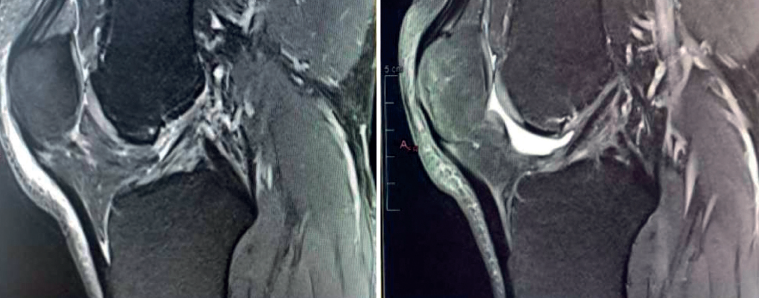

The main indication for primary ACL repair is in patients with high-grade complete or partial tears corresponding to types 1 or 2 of the original Shermanclassification(7), i.e. in avulsions of the femoral insertion (type 1) or in proximal tears leaving 75-90% of the distal ligament intact (type 2). In any case, good quality of the remaining tissue is essential. It should be noted that the incidence of tears of this kind appears to be greater in individuals over 35 years of age(7). This is not a problem, given that the incidence of re-rupture following ACL repair is higher in younger patients under 21 years of age(8,9).

With regard to the timing of surgery, the operation is ideally performed within 6 weeks of the injury(10,11,12), although good results have also been published repairing chronic tears in which the torn ACL stump heals over the posterior cruciate ligament (PCL)(13,14).

We now know from the histological study of ACL remnants after rupture that the ligament has some intrinsic capacity for spontaneous healing, as evidenced by the presence of vascular buds, nerve endings and cells with healing capacity in the remnant tissue(3). Further evidence of this self-repairing capacity can be found in the good functional results published in some patients treated on a conservative basis, especially older individuals with lesser physical demands(4)(Figure 1).